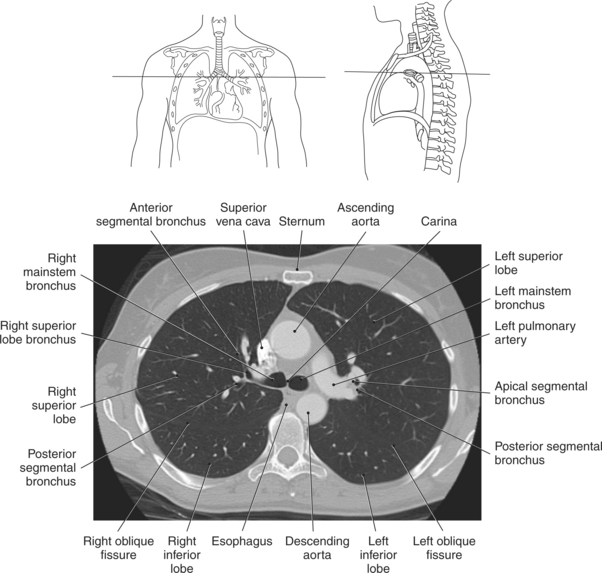

The lungs are the organs of respiration, where gaseous exchange occurs between the respiratory air and blood. They are composed of a spongelike material, the parenchyma, and surrounded by a layer of serous membrane. The large conical-shaped lungs extend up to or slightly above the level of the first rib at their apex and down to the dome of the diaphragm at their wide concave-shaped bases or diaphragmatic surfaces (Figure 6.9). Each lung has a mediastinal or medial surface that is apposed to the mediastinum, and a costal surface that is apposed to the inner surface of the rib cage. Each lung also has an inferior, anterior, and posterior border. The inferior border extends into the costodiaphragmatic recess of the pleural cavity, and the anterior border of each lung extends into the costomediastinal recess of the pleural cavity (Figure 6.10). Two prominent angles can be identified at the medial and lateral edges of the lung bases. The medial angle is termed the cardiophrenic sulcus, and the lateral angle is termed the costophrenic sulcus (Figure 6.11 and 6.12). The lungs are divided into lobes by fissures that are lined by pleura and may extend as far as the hilum (Figure 6.13). The right lung has three lobes (superior [upper], middle, and inferior [lower]), whereas the left lung has just superior (upper) and inferior (lower) lobes (Figures 6.6 and 6.11 through 6.13). The inferior lobe of the right lung is separated from the middle and superior lobes by the oblique fissure, termed oblique because of its posterosuperior to anteroinferior course. Separating the middle lobe from the superior lobe is the horizontal fissure (Figures 6.9 and 6.14, A). An oblique fissure also separates the superior and inferior lobes of the left lung (Figure 6.11). The left lung has a large notch on the medial surface of its superior lobe called the cardiac notch and a tonguelike projection off its inferoanterior surface termed the lingula. Each lung has an opening on the medial surface termed the hilum (Figures 6.14 through 6.16). This opening acts as a passage for mainstem bronchi, blood vessels, lymph vessels, and nerves to enter or leave the lung and is commonly referred to as the root of the lung.

The trachea bifurcates into the left and right mainstem (primary) bronchi at approximately the level of T5. This location is commonly referred to as the carina (Figure 6.9). The right main bronchus is wider, shorter, and more vertical in orientation then the left. At the hilum the mainstem bronchi enter the lung and divide into secondary or lobar bronchi. Secondary bronchi correspond to the lobes of the lungs, thus with three divisions on the right (superior, middle, inferior) and two divisions on the left (superior and inferior) (Figure 6.9, and 6.18 through 6.20). There is further division of the secondary bronchi into tertiary or segmental bronchi that extend into each segment of the lobes (bronchopulmonary segments) (Figure 6.21 and Table 6.1). There are typically 10 segments within each lung. Each bronchopulmonary segment is functionally independent and can be individually removed surgically. The bronchial tree continues to divide many times into smaller bronchi, then into bronchioles (Figure 6.22). Each bronchiole continues to divide until it reaches the terminal end as alveoli, which are the functional units of the respiratory system. Gaseous exchange between alveolar air and capillary blood occurs through the wall of the alveoli.

Throughout its course in the mediastinum, the trachea runs anterior to the esophagus. In cross section, the trachea appears as a round air-filled structure to the point at which it bifurcates at the carina (Figures 6.9 and 6.18). The esophagus appears as an oval-shaped structure that descends through the diaphragm to enter the stomach at the gastroesophageal junction (Figures 6.27 and 6.28).